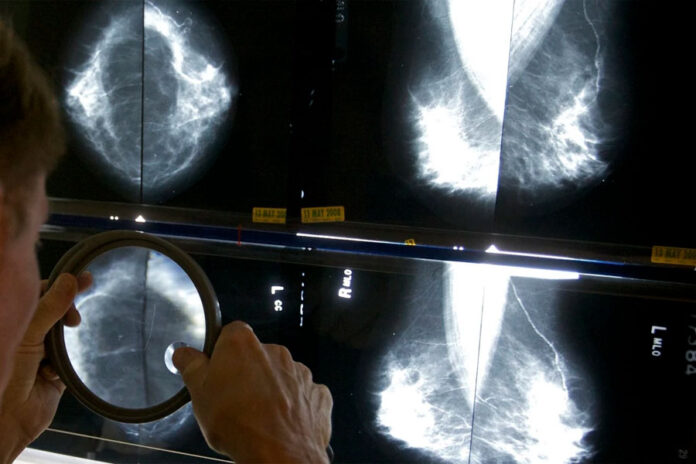

Cada año, unas 50.000 mujeres en Estados Unidos son diagnosticadas con carcinoma ductal in situ —o carcinoma intraductal—, en el que las células que recubren los conductos mamarios del seno se vuelven cancerosas, pero el tejido mamario cercano permanece sano. Muchas optan por someterse a cirugía, aunque no está claro si podrían en cambio adoptar un enfoque de “esperar y ver” bajo un monitoreo más frecuente.

El hallazgo se basa en el seguimiento de más de 950 pacientes estadounidenses asignadas aleatoriamente a cirugía o monitoreo activo. Todas tenían CDIS de bajo riesgo sin signos de cáncer invasivo. Tenían el tipo de carcinoma intraductal que responde a los medicamentos bloqueadores de hormonas y muchas en el estudio tomaron esos medicamentos como parte de su tratamiento.

Entre las pacientes en el grupo de monitoreo, los cambios detectados en una mamografía provocarían una biopsia. También podrían optar por la cirugía en cualquier momento por cualquier motivo.

Ella se somete a mamografías cada seis meses para mantener vigilancia sobre el CDIS en su seno derecho, que no ha avanzado. Las mamografías detectaron un pequeño cáncer en su otro seno en 2023, no relacionado con el carcinoma intraductal. Se sometió a una tumorectomía para eliminarlo.